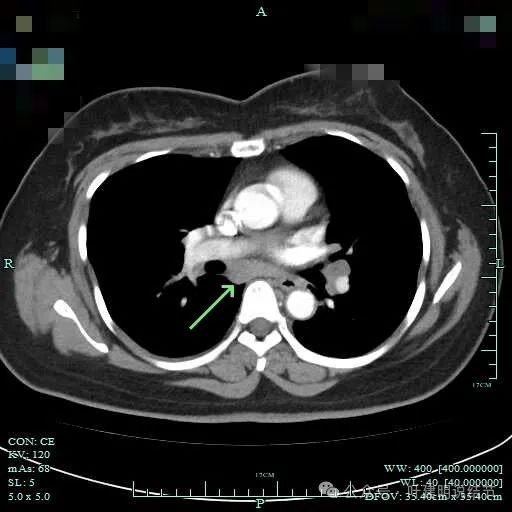

再看2024年7月份的影像:

病灶纵隔窗上是软组织影,表面不平,形态不规则。上腔静脉旁有肿大淋巴结。

病灶有血管与之相连,淋巴结更显得明显了。

肺窗上见与上腔静脉紧贴着,病灶边缘稍显模糊。

右侧腔静脉旁肿大淋巴结。